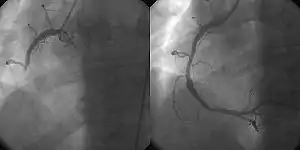

![]() A coronary angiogram showing the circulation in the left main coronary artery and its branches. | |